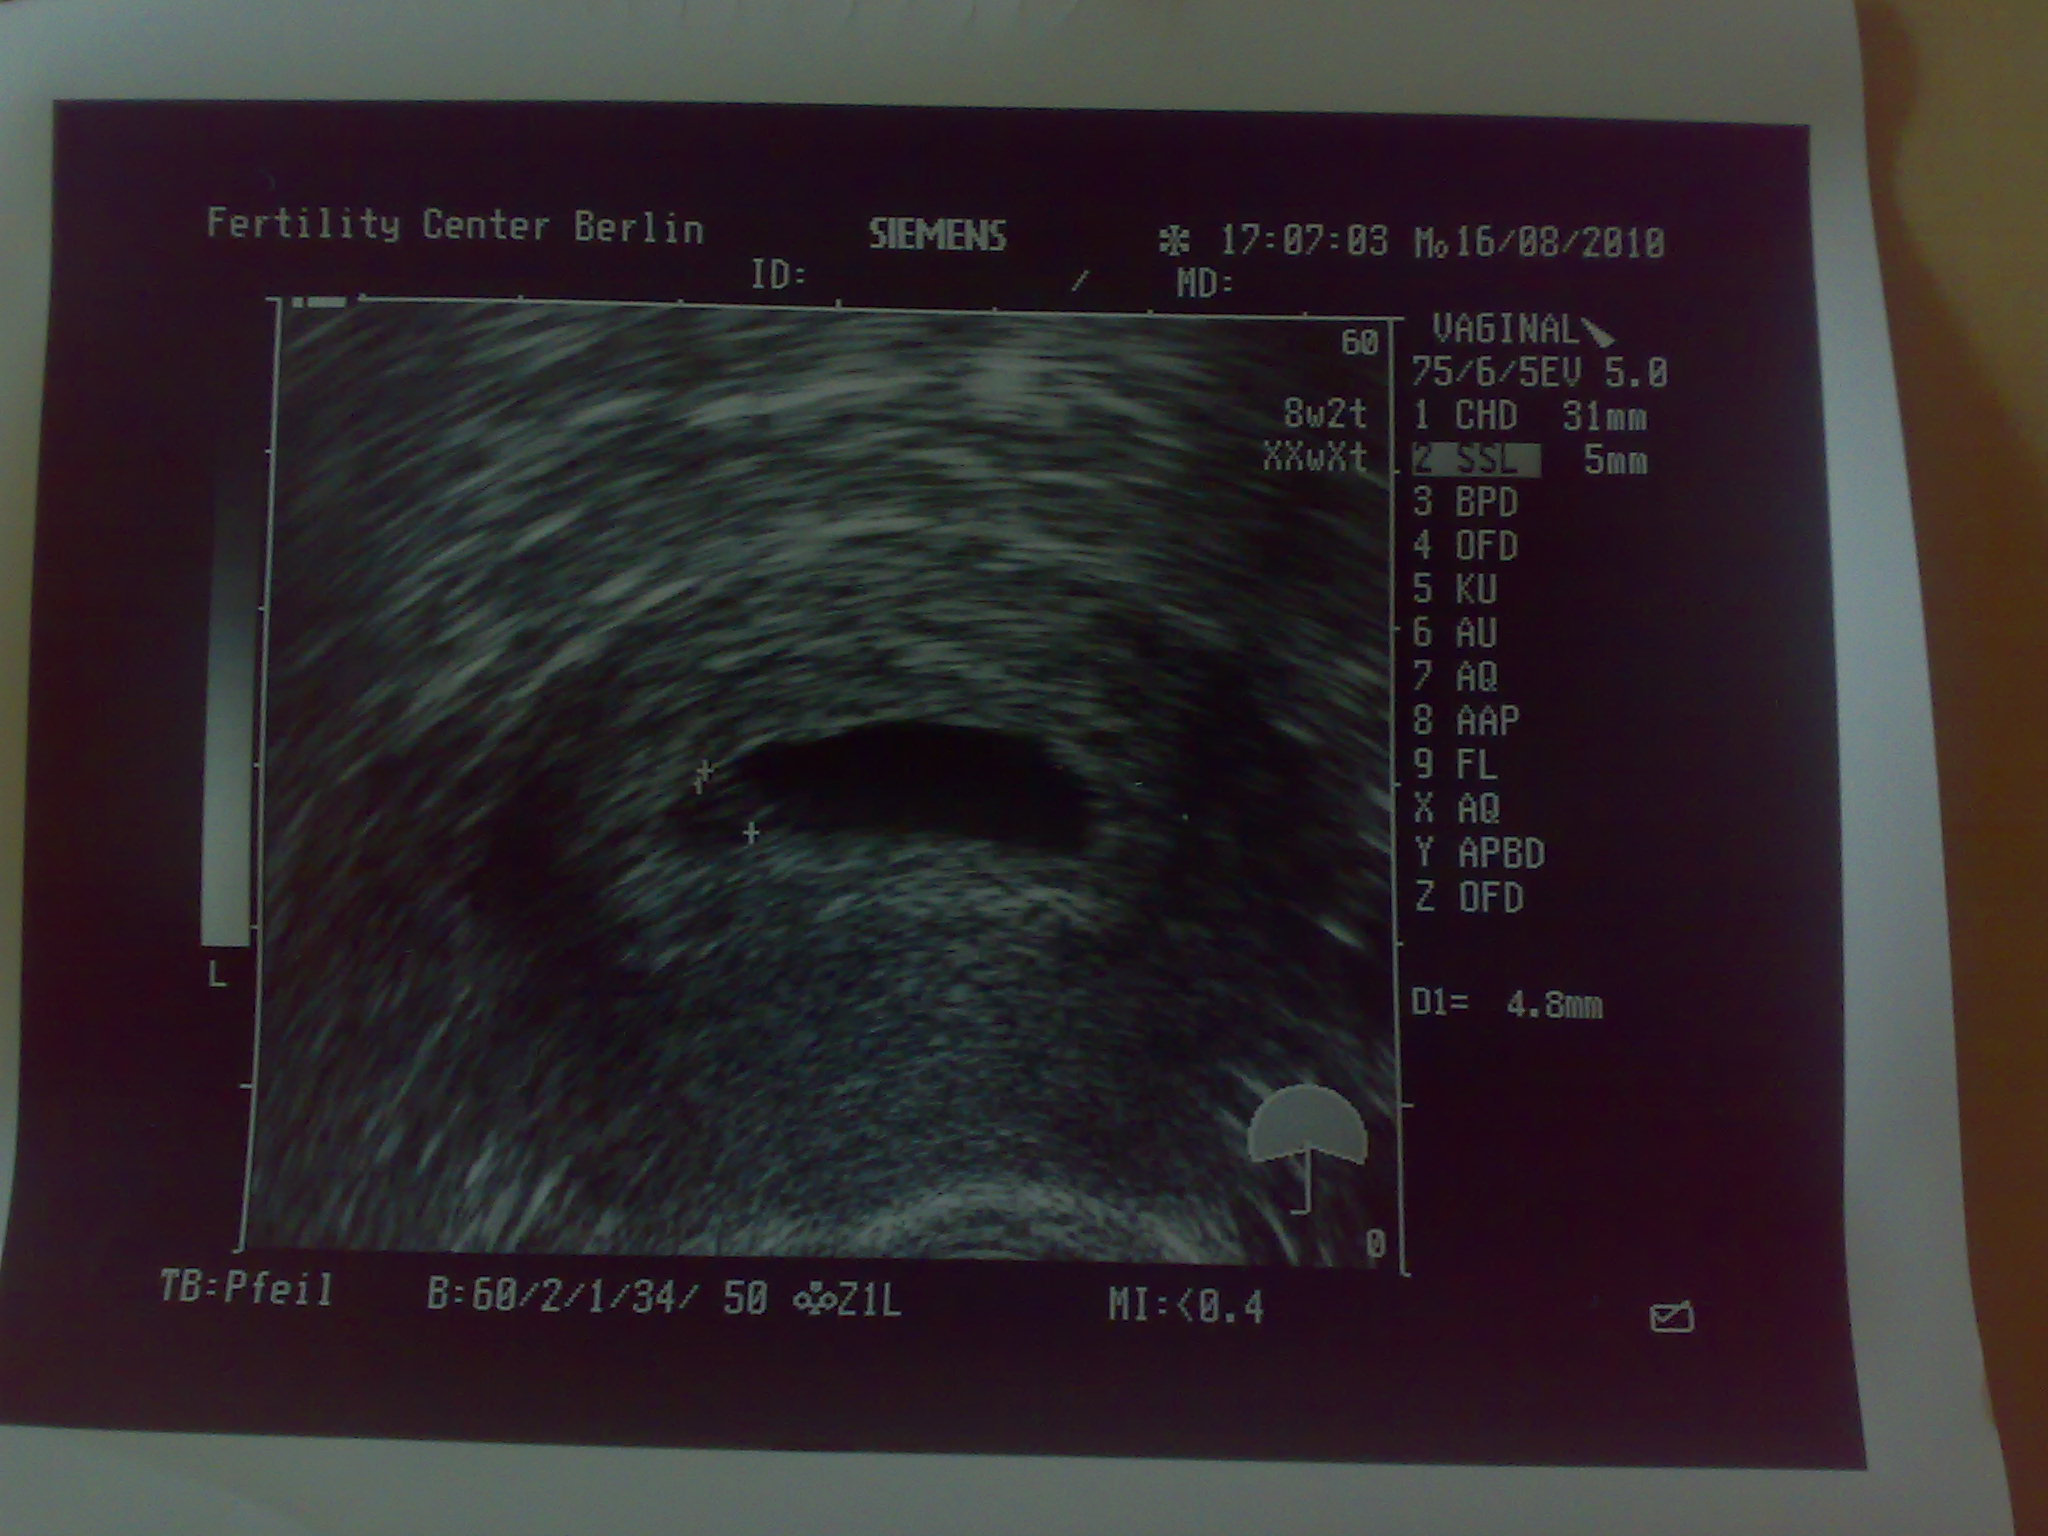

Fruchthöhle mit 17.6 mm samt Dottersack und kleinen Pünktchen drin waren zu sehen, aber leider noch kein Herzschlag. Durch die Größe der Fruchthöhle hat er meine SS auf 5+6 zurückdatiert, das passt dann auch besser zu meinem HCG.

Die Lage der Fruchthöhle, so hat er erklärt, wäre prima, mittendrin und nicht am Rand, und rundherum die Schichten zur Ernährung wären prima aufgebaut. Schleimhaut hat er auch gemessen und auf 38 mm datiert. Soweit alles bestens, aaaaaaaaaaber solange kein Herzschlag zu sehen ist, wäre die Wahrscheinlichkeit eben nur bei 60% auf eine Lebendgeburt. Ab Herzschlag 97%....